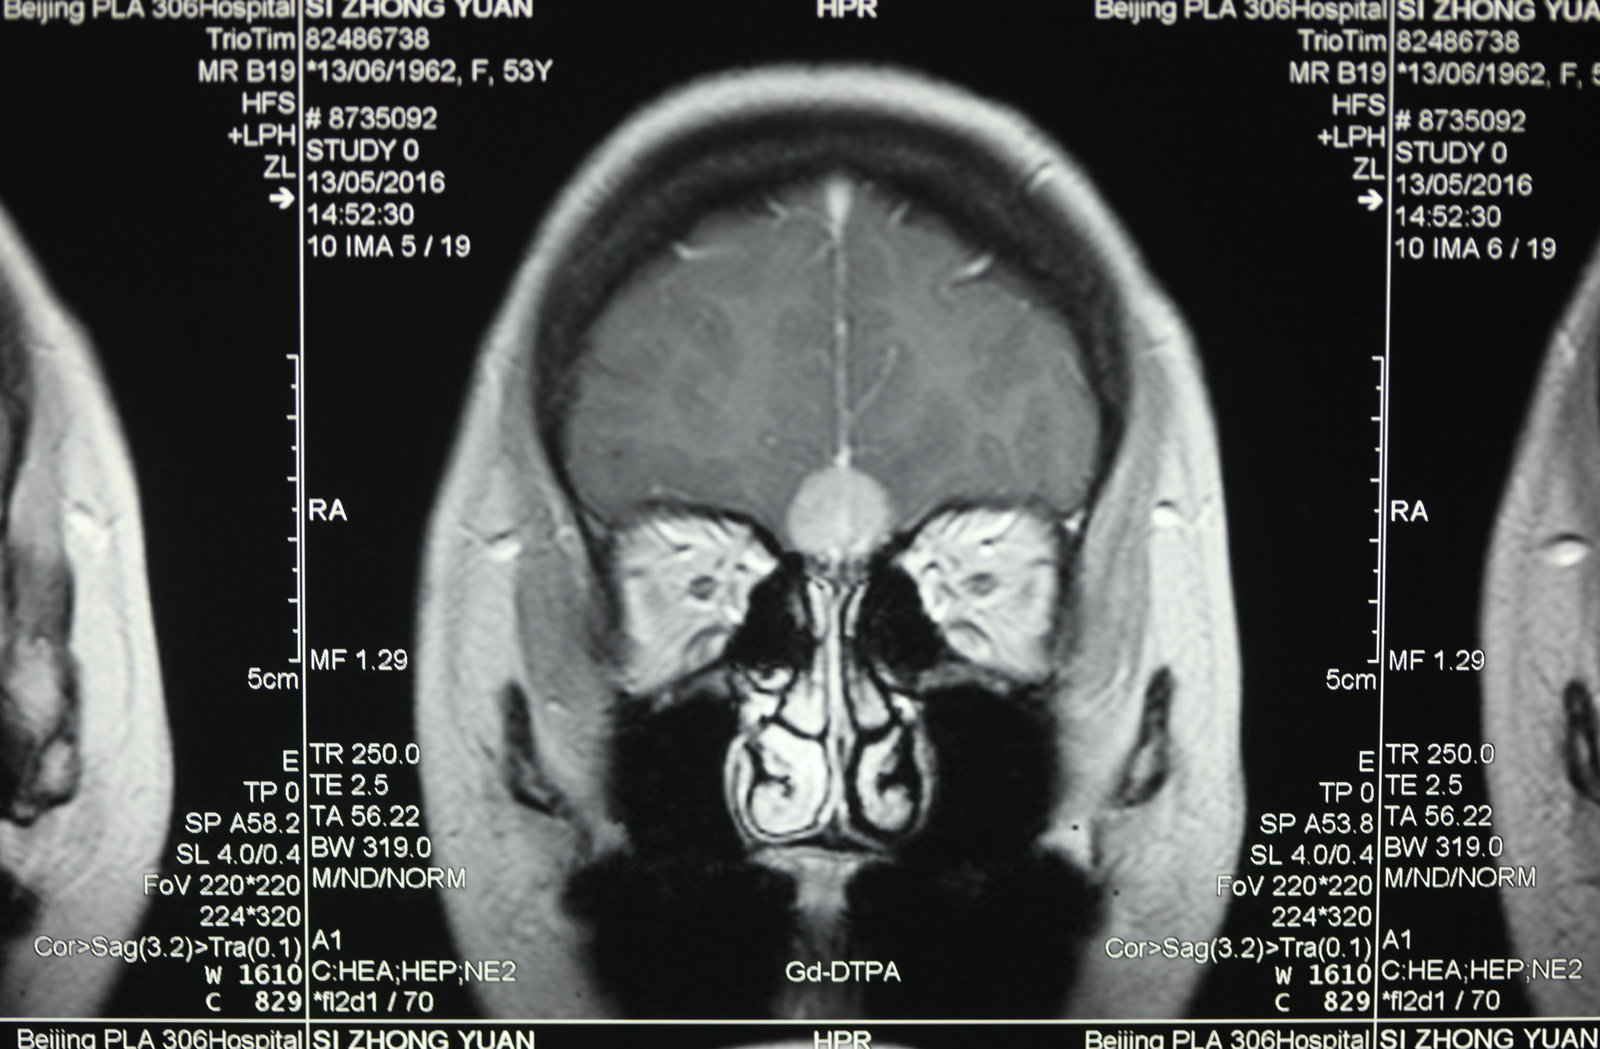

显微神经外科学是以应用手术显微镜为标志,但是,我们决不能片面的将显微神经外科学理解为只要手术中使用手术显微镜就是显微神经外科手术。而显微神经外科学的正确概念,足指以近代影像学为诊断基础,一整套与显微手术相匹配的手术设备、显微神经外科手术器械为保证的,以颅内病灶为中心的手术。显微神经外科学不仅是技术,更重要的是概念的更新。

1.以病灶性为中心手术,减少脑组织损伤:显微神经外科手术将经典神经外科“脑叶范围手术”,推向“病灶性手术”水平,尽量减少干扰脑组织,探索出新的手术入路。譬如,翼点入路、经岩骨入路以及额眶颧入路,这些具有代表性显微手术入路的共同特点是,牺牲部分颅底骨结构获得手术空间,经过脑外抵达病灶,尽量减少对脑的牵拉和损伤。20世纪70年代,Yasargil提出利用颅内自然的解剖间隙和经脑外到达病灶部位,处理病变,降低手术创伤,成为了显微神经外科手术的基本概念。随着对脑功能认识的逐步深入,手术中还对各种神经和脑血流进行监测,加大了对脑和神经的功能保护。

将手术显微镜和显微神经解剖结合,会使许多常规的神经外科手术得到进一步完善,如脊髓的切除、动脉瘤的夹闭等,并开创了以往神经外科医生不能施行的手术。由于对显微神经解剖认识的深入,医生能够以较小的脑牵开或皮层结构切开,经过神经血管间隙,安全准确地达到脑深部病灶,进行微损伤的手术切除。总之,显微神经解剖和显微外科技术结合,可在微创下切除以往不能手术切除的病变。而应用手术显微镜进行神经外科解剖研究和神经外科教学是对以往的肉眼神经解剖研究的全新修正,它使肉眼观测困难的微小结构和纤细神经清晰可辨,属于全新的领域。 手术显微镜的应用又使医生感到手术操作在灵活性和精确性方面受限,因此又有学者开始探索机器人辅助手术,这将开创精细外科技术的新境界,当然它也要求有新的显微解剖知识与其适应。其他新技术的发展也需要以精确的显微神经解剖知识为基础,如在血管内栓塞治疗动脉瘤时,需要详尽了解载瘤动脉、穿通动脉及其解剖变异经过缜密的开颅设计,可达到颅底任何部位。将显微神经外科解剖研究结合影像学定位,利用脑表面的沟裂建立细小孔道,一些脑深部解剖能理想的显露。显微解剖研究也研究了一些新的手术入路,如经脉络膜入第三脑室手术入路、经鼻腔入蝶窦的垂体瘤手术入路等。在未来,通过更深入的显微外科解剖学研究,还会有一些新的更好的手术入路研究出来。另外一些新的手术技术的改进和完善也需要对显微外科解剖的深入理解。 随着神经精细结构显露技术的显著提高,显微解剖照片准确鲜明,生动活泼,非常优美,适合于神经外科学习和参考。